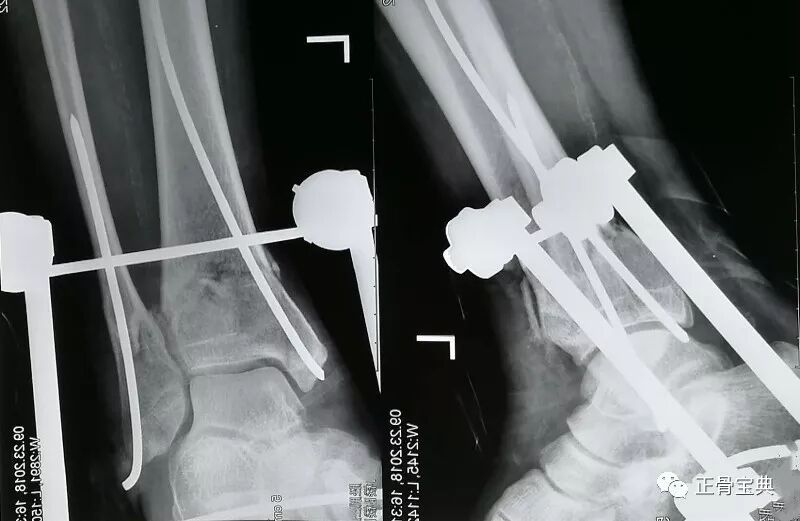

左腓骨骨折 治療-左侧腓骨远端骨折怎么治疗? 检查方法:左踝关节正侧位X线表现左踝关节在位,关节面光滑,关节间隙未见明显狭窄,左侧腓骨远端见透亮影,余骨未见明显骨折征象。 结论考虑左侧腓骨远端骨折是个女孩17了。 溜冰时摔倒 X线表现 左踝关节在位,关节面光滑,关节间隙未见明显狭窄,左侧腓骨远端见透亮影,余骨未见明显骨折征象。 是个女孩 17了。 溜冰时摔倒的 病案1:男性, 岁。左小腿外伤19小时就诊, 查体 左小腿畸形, 假关节活动, 骨摩擦感,胫前伤口3cm, 骨端外露, x线显示左胫骨中段粉碎性骨折, 临床诊断 左胫骨中段开放性粉碎性骨折, 正确的急诊治疗 a 急诊手术, 钢板螺钉内固定 b 清创缝合, 小夹板固定 c 伤口

胫腓骨骨折在长管状骨 骨折中最常见。 胫腓骨干骨折 胫骨浅居皮下,缺乏肌肉附盖,故骨折后极易被骨折断端穿破皮肤。 多见儿童和青壮年。多为直接暴力所致。若发生在中下段,易引起延迟愈合或不愈合。 重定不好会产生创伤性关节炎。 腓骨骨折は転倒・転落で足首を強打した又は強く捻った際などに足首付近(外くるぶしの上下)で起こる事が多く、受傷すると痛みにより歩行困難となります。 単純に骨折しているだけでなく、脛骨と腓骨、腓骨と足部の靭帯も損傷している可能性もあるので、受傷後は必ず整形外科に受診しましょう。 腓骨骨折の診断 骨折はレントゲンにて診断可能です。 しかし、精査が必要な場